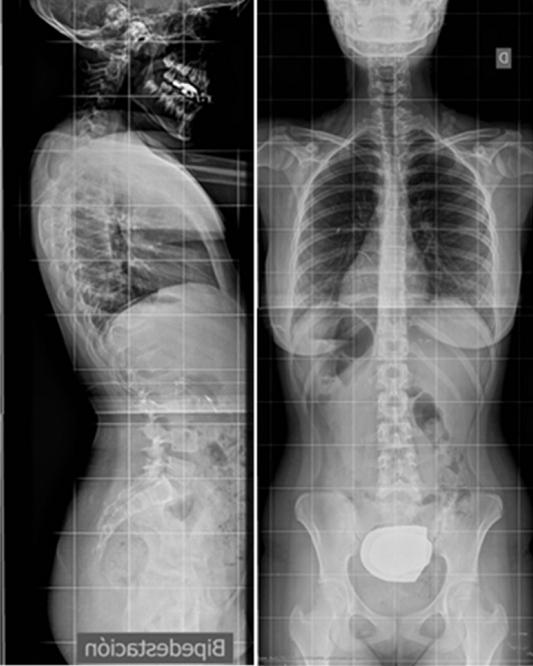

La escoliosis puede presentar una o varias curvas y en su evolución, no mejora (Figura 8). Por eso, se hace imprescindible su seguimiento con sucesivas telerradiografías, lo cual obliga, éticamente, a optimizar su estudio8.

Figura 8. Telerradiografía de escoliosis de una paciente a lo largo del tiempo. Mostrar/ocultar

La localización de estas curvas puede ser torácica, lumbar, o toraco-lumbar. Normalmente existe una, la llamada curva principal, sobre la que asienta la mayor deformidad rotacional. Recordemos que la escoliosis es una deformidad tridimensional en la que el raquis gira sobre sí mismo. Generalmente se acompaña de otra curva llamada secundaria a la primera en un intento de equilibrar en conjunto la columna.